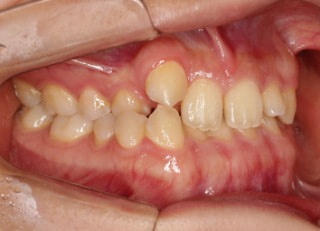

治療後(2年11ヶ月後)